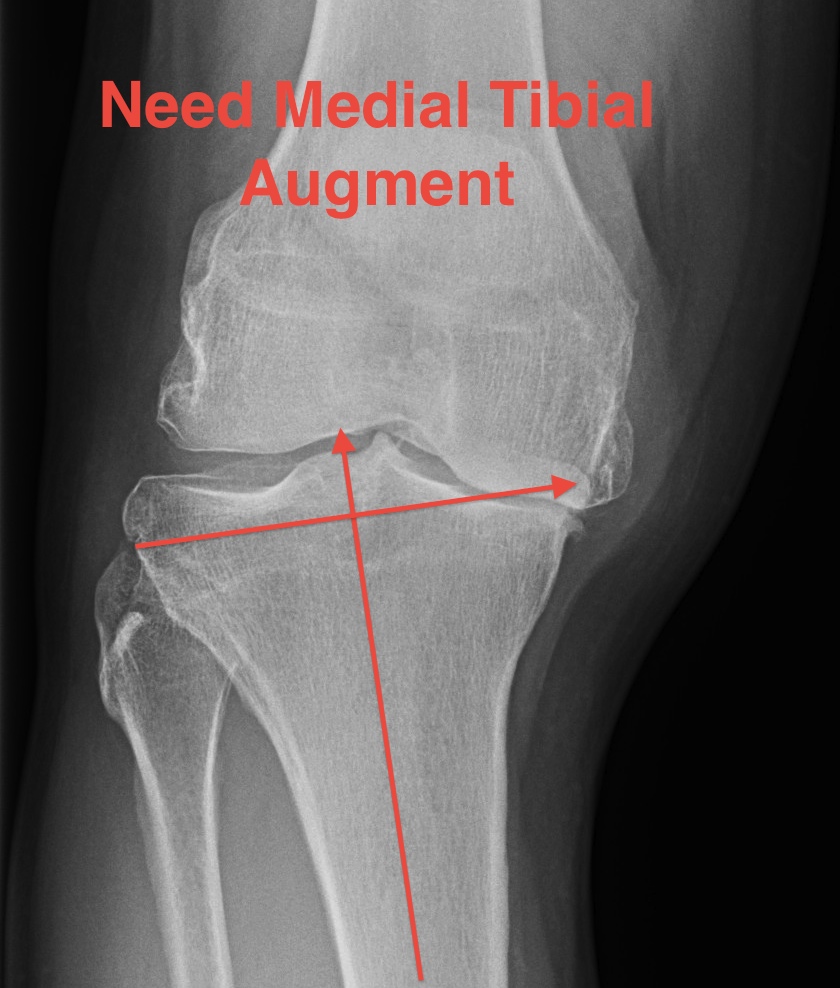

Severe varus deformity

Problem

- 10 mm from lateral side does not take medial bone

- do not cut to level of medial defect as cancellous bone of the tibia becomes weak

Solution

- stay subchondral on lateral side

- never more than 10 mm cut lateral side

- build up medial side

Options

1. Cement

2. Autologous bone graft

- may have enough in primary

- from posterior or distal femoral condyles

- supplement with 2 screws

3. Augments

- 5 - 10 mm

- use stems if use augments

- offsets forces to the diaphysis (up to 30%)